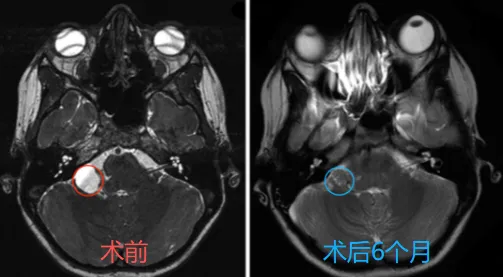

一台原本用于抢救脑出血的急诊手术,竟在术中意外发现了一枚此前毫无症状的隐匿小肿瘤。是冒险一并处理,还是暂且搁置留待观察?...